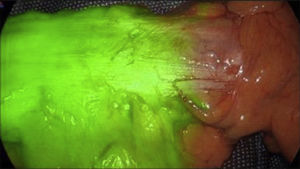

Based on these results, we can conclude that ICG-FA is an effective method to help reduce anastomotic leaks after colorectal surgery5–14 (Fig. 1).

One of the associated problems is that the high fluorescence of the liver can prevent or hinder the identification of the biliary tree and, especially if the injection has been very recent, prevents correct visualization of the bile duct.30 To avoid these issues, some authors have proposed earlier preoperative injection or direct gallbladder injection,31–33 although it is a somewhat cumbersome technique and not always possible. For the reasons previously mentioned and for perfect definition of the bile duct with less hepatic contrast, ICG should be administered 3−8 h before surgery,29–34 although new vision systems enable injection even during anesthesia induction (Fig. 2).